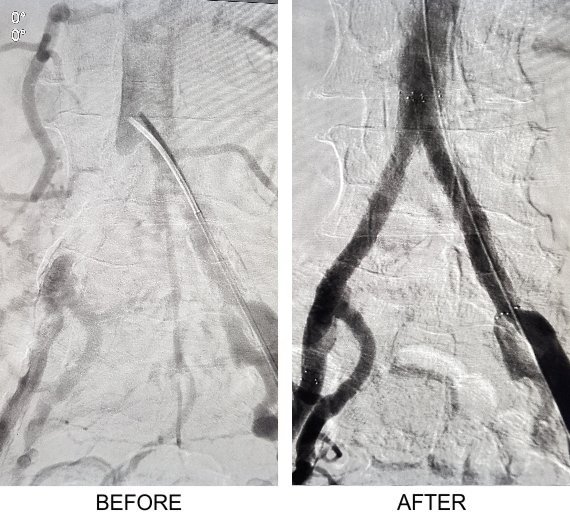

- Bypass: Often, long segment blockages or multilevel blockages are better dealt with by surgical bypass. Surgical bypass can be performed by using patients own vein or a synthetic graft and can be performed from the abdomen to the foot depending on the level and extent of arterial blockage. These procedures will not cure PAD, but they can improve the blood circulation to your legs and your ability to walk and thus prevent amputation.

Femoro Popliteal Bypass using Vein Graft

Supra-Celiac Aorto Femoral Bypass

Popliteo-Distal Bypass

Successful Treatments